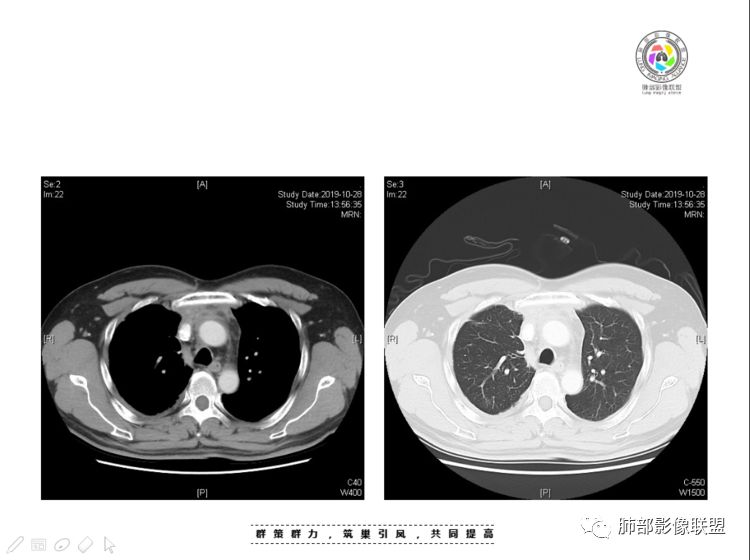

南边:大家看看前纵隔的病灶,符合肿瘤吗脂肪,周围密度增高

三个石头:比较散;像炎症的蔓延生长南边:是,这些看着心里不踏实觉得把这个纳入肿瘤去考虑是否合适总觉得边缘收缩的、散在的朝周围蔓延;中央还跨过脂肪,朝对侧胸膜蔓延把这个与囊性病变连到一起去考虑是否还需要斟酌一下因为这个就方向差异大了南边:连在一起,囊实性,边界不清,自然考虑恶性:如果独立,囊张力高、边界清楚,间隔,自然朝良性考虑:

我认为囊张力高,积液中的气体均在周围,外侧、下方,囊内有间隔:各腔密度不一致;提示:囊腔属于前纵隔,不是包裹性积液;现在的问题:囊腔与内侧的病灶是否是一体的

南边:我总觉得这个纵隔内不像是一个肿块的改变,扁平,周围蔓延:有符合炎性的的特点,或者肿瘤的侵犯;但是肿瘤的侵犯,不大符合,实性部位的边缘过于柔和,没有毛糙的侵犯边缘。